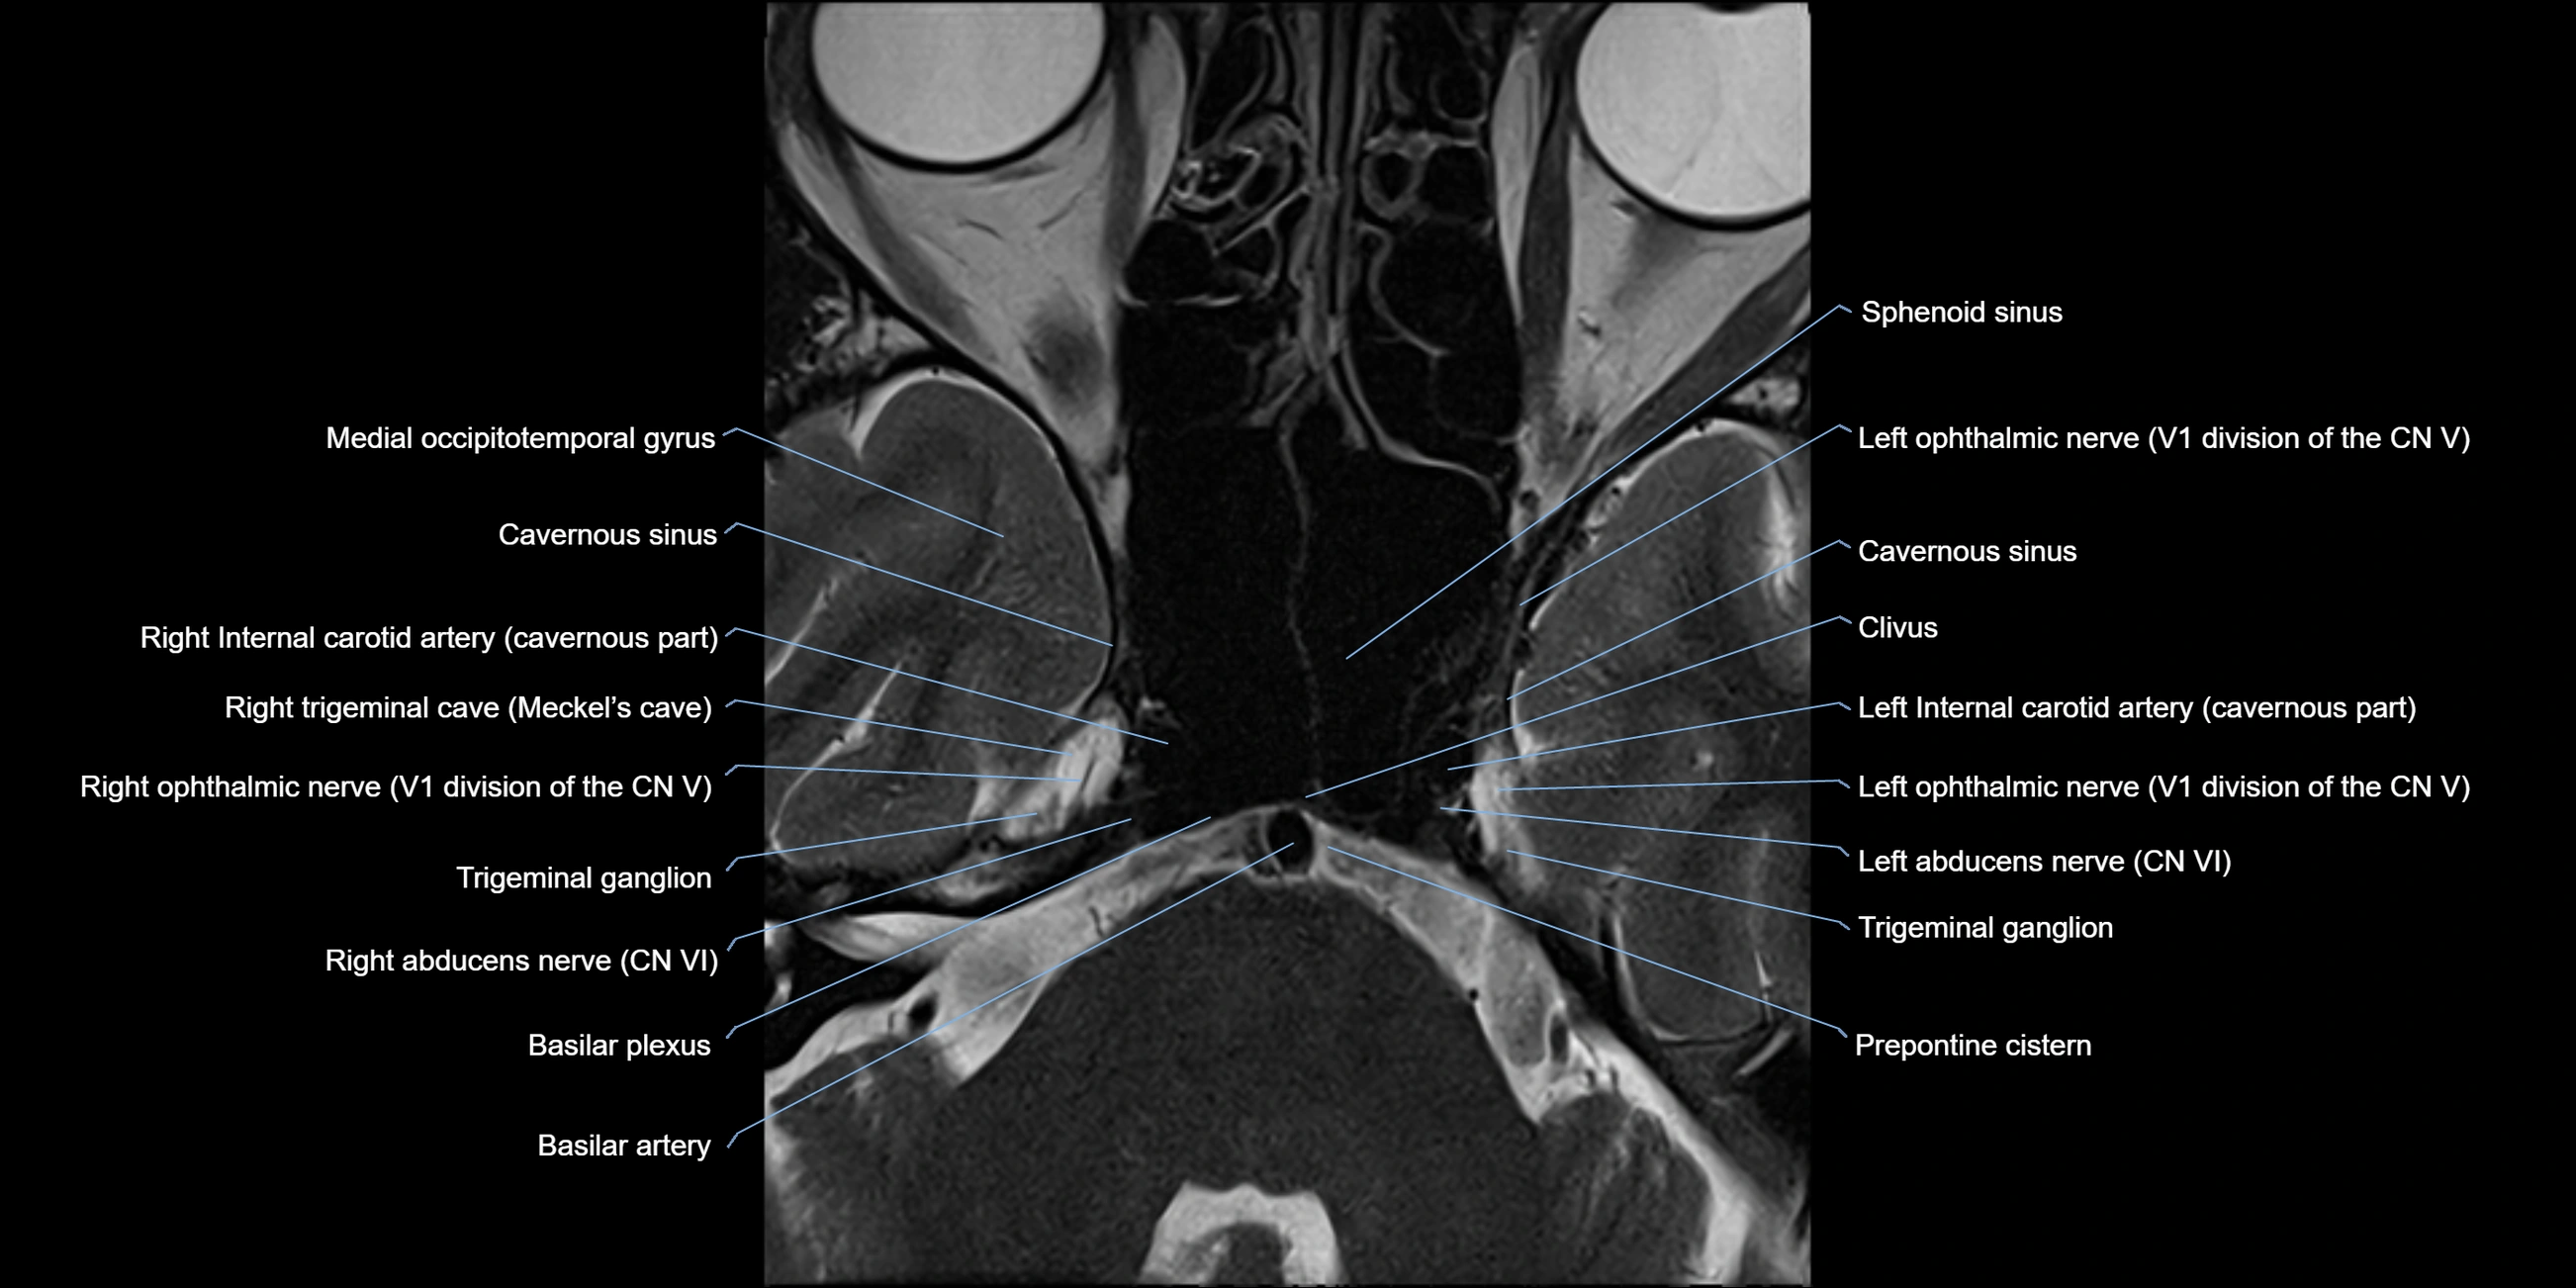

MRI Appearance

The abducens nerve is a small, thin, linear structure

Best visualized on high-resolution T2-weighted 3D MRI sequences (e.g., FIESTA or CISS)

Seen as a hypointense (dark) line running from the brainstem at the pontomedullary junction, traversing the prepontine cistern, and entering Dorello’s canal under the petrosphenoidal ligament, then into the cavernous sinus, and finally the orbit

May be challenging to visualize in standard MRI due to its small size

Pathology may be inferred by absence, displacement, or enhancement of the nerve

MRI images